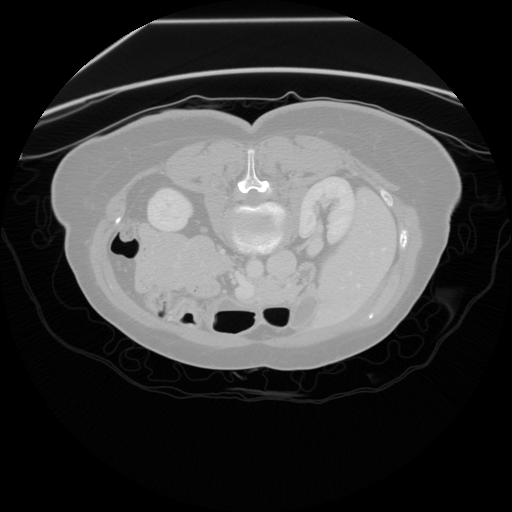

Figure 1: Example of moving (top) and fixed (bottom) image pairs. From left to right: brain MRI (T2w, T1w, T1Gd), abdomen CT from different subjects, retinal OCTA choroid, and retinal OCTA SCP scans

To address this problem, we propose a meta-learning-based registration meth-od that can efficiently use data from different domains. Specifically, we integrate an unsupervised learning-based registration model in a gradient-based meta-learning framework. The registration model is first trained using multiple registration datasets and then performs task-level learning using the multi-task data. The meta-learner finds an initialization point which can quickly adapt to various registration problems. After that, fine tuning is performed with the data of the target domain and applied to the test set. To demonstrate superiority, we trained the model for various 2D registration tasks from retinal Optical Coherence Tomography Angiography (OCTA) choroid, abdomen CT, and brain MRI scans and tested it on a registration of retinal OCTA Superficial Capillary Plexus (SCP) scans as shown in Fig. 1.

In our experiment, we used four datasets including retinal OCTA SCP, retinal OCTA choroid, abdomen CT, and Brain MRI. Both OCTA SCP and choroid datasets contained 368 moving and fixed image pairs collected from local university hospital, some of which were taken from same subjects at different times. The abdomen CT and brain MRI images were obtained from public Decathlon dataset [15]. Here, we define three tasks according to modality (T1w, T1Gd, and T2w) from the brain MRI dataset and two tasks in the abdomen CT dataset. Each 3D volume was divided in multiple axial slices and adjacent two slices were defined as a (M,F)𝑀𝐹(M,F) pair. All images were resized to a size of 400×400400400400\times 400 and histogram equalization was applied. Also, the range of intensity was rescaled to [0,1]. For training, we defined a set of five tasks as the source task set Tsource=subscript𝑇𝑠𝑜𝑢𝑟𝑐𝑒absentT_{source}= TbrainT1subscript𝑇𝑏𝑟𝑎𝑖𝑛𝑇1T_{brainT1}, TbrainT1Gdsubscript𝑇𝑏𝑟𝑎𝑖𝑛𝑇1𝐺𝑑T_{brainT1Gd}, TbrainT2subscript𝑇𝑏𝑟𝑎𝑖𝑛𝑇2T_{brainT2}, Tabdomensubscript𝑇𝑎𝑏𝑑𝑜𝑚𝑒𝑛T_{abdomen}, TChoroidsubscript𝑇𝐶𝑜𝑟𝑜𝑖𝑑T_{Choroid}. For evaluation, retinal OCTA SCP dataset was used as target domain data Dtargetsubscript𝐷𝑡𝑎𝑟𝑔𝑒𝑡D_{target}. It was divided into a fine-tuning set Tfinetunesubscript𝑇𝑓𝑖𝑛𝑒𝑡𝑢𝑛𝑒T_{fine-tune} (294 pairs) and a test set Ttestsubscript𝑇𝑡𝑒𝑠𝑡T_{test} (74 pairs). For evaluation, we manually labeled 20similar-to\sim30 bifurcation points on image pairs in Ttestsubscript𝑇𝑡𝑒𝑠𝑡T_{test}.